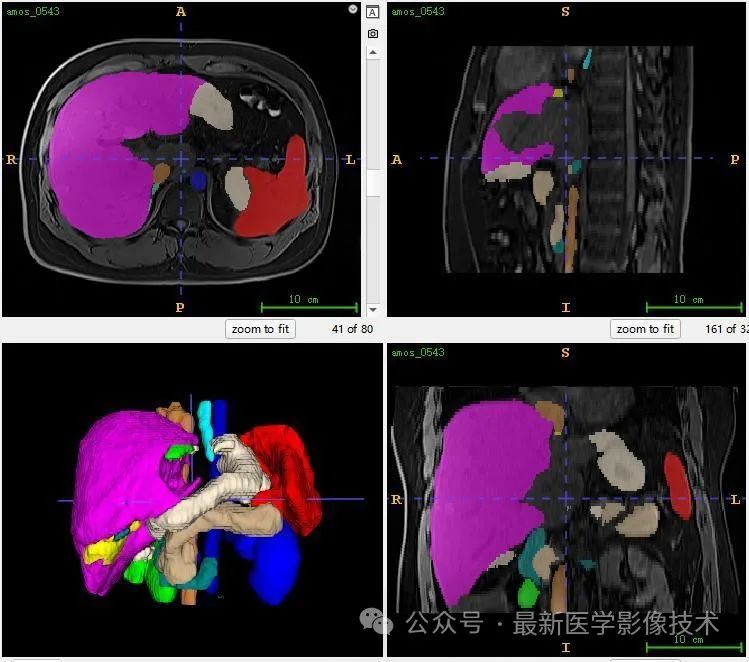

12、验证集分割结果

左图是金标准结果,右图是预测结果。

13、测试集分割结果